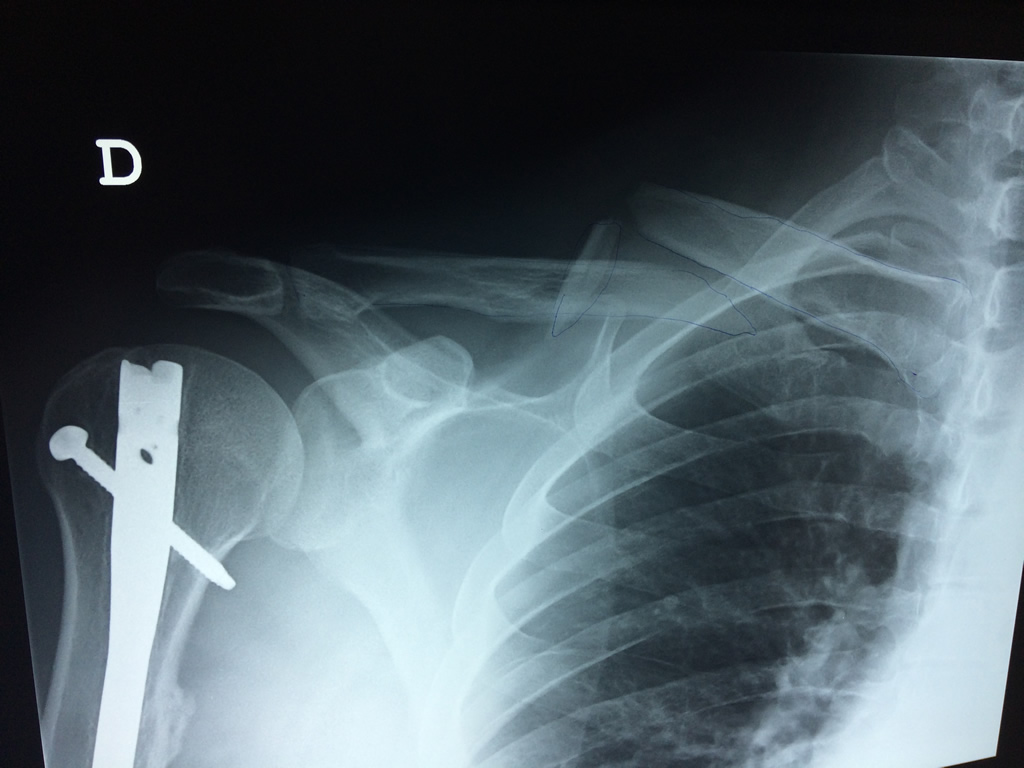

Cirugias en El Salvador - Clavícula

La clavícula es un hueso largo, con forma de "S" itálica, situado en la parte anterosuperior del tórax. Junto con la escápula forman la cintura escapular. Se puede palpar por toda su longitud y se extiende del esternón al acromion de la escápula, siguiendo una dirección oblicua lateral y posterior.